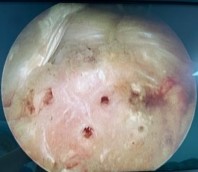

Hình 2.27. Tạo vi tổn thương sau khi buộc chỉ khâu CX

* Nguồn: ảnh chụp trong mổ của BN Lê Cao S, số bệnh án 1911250706